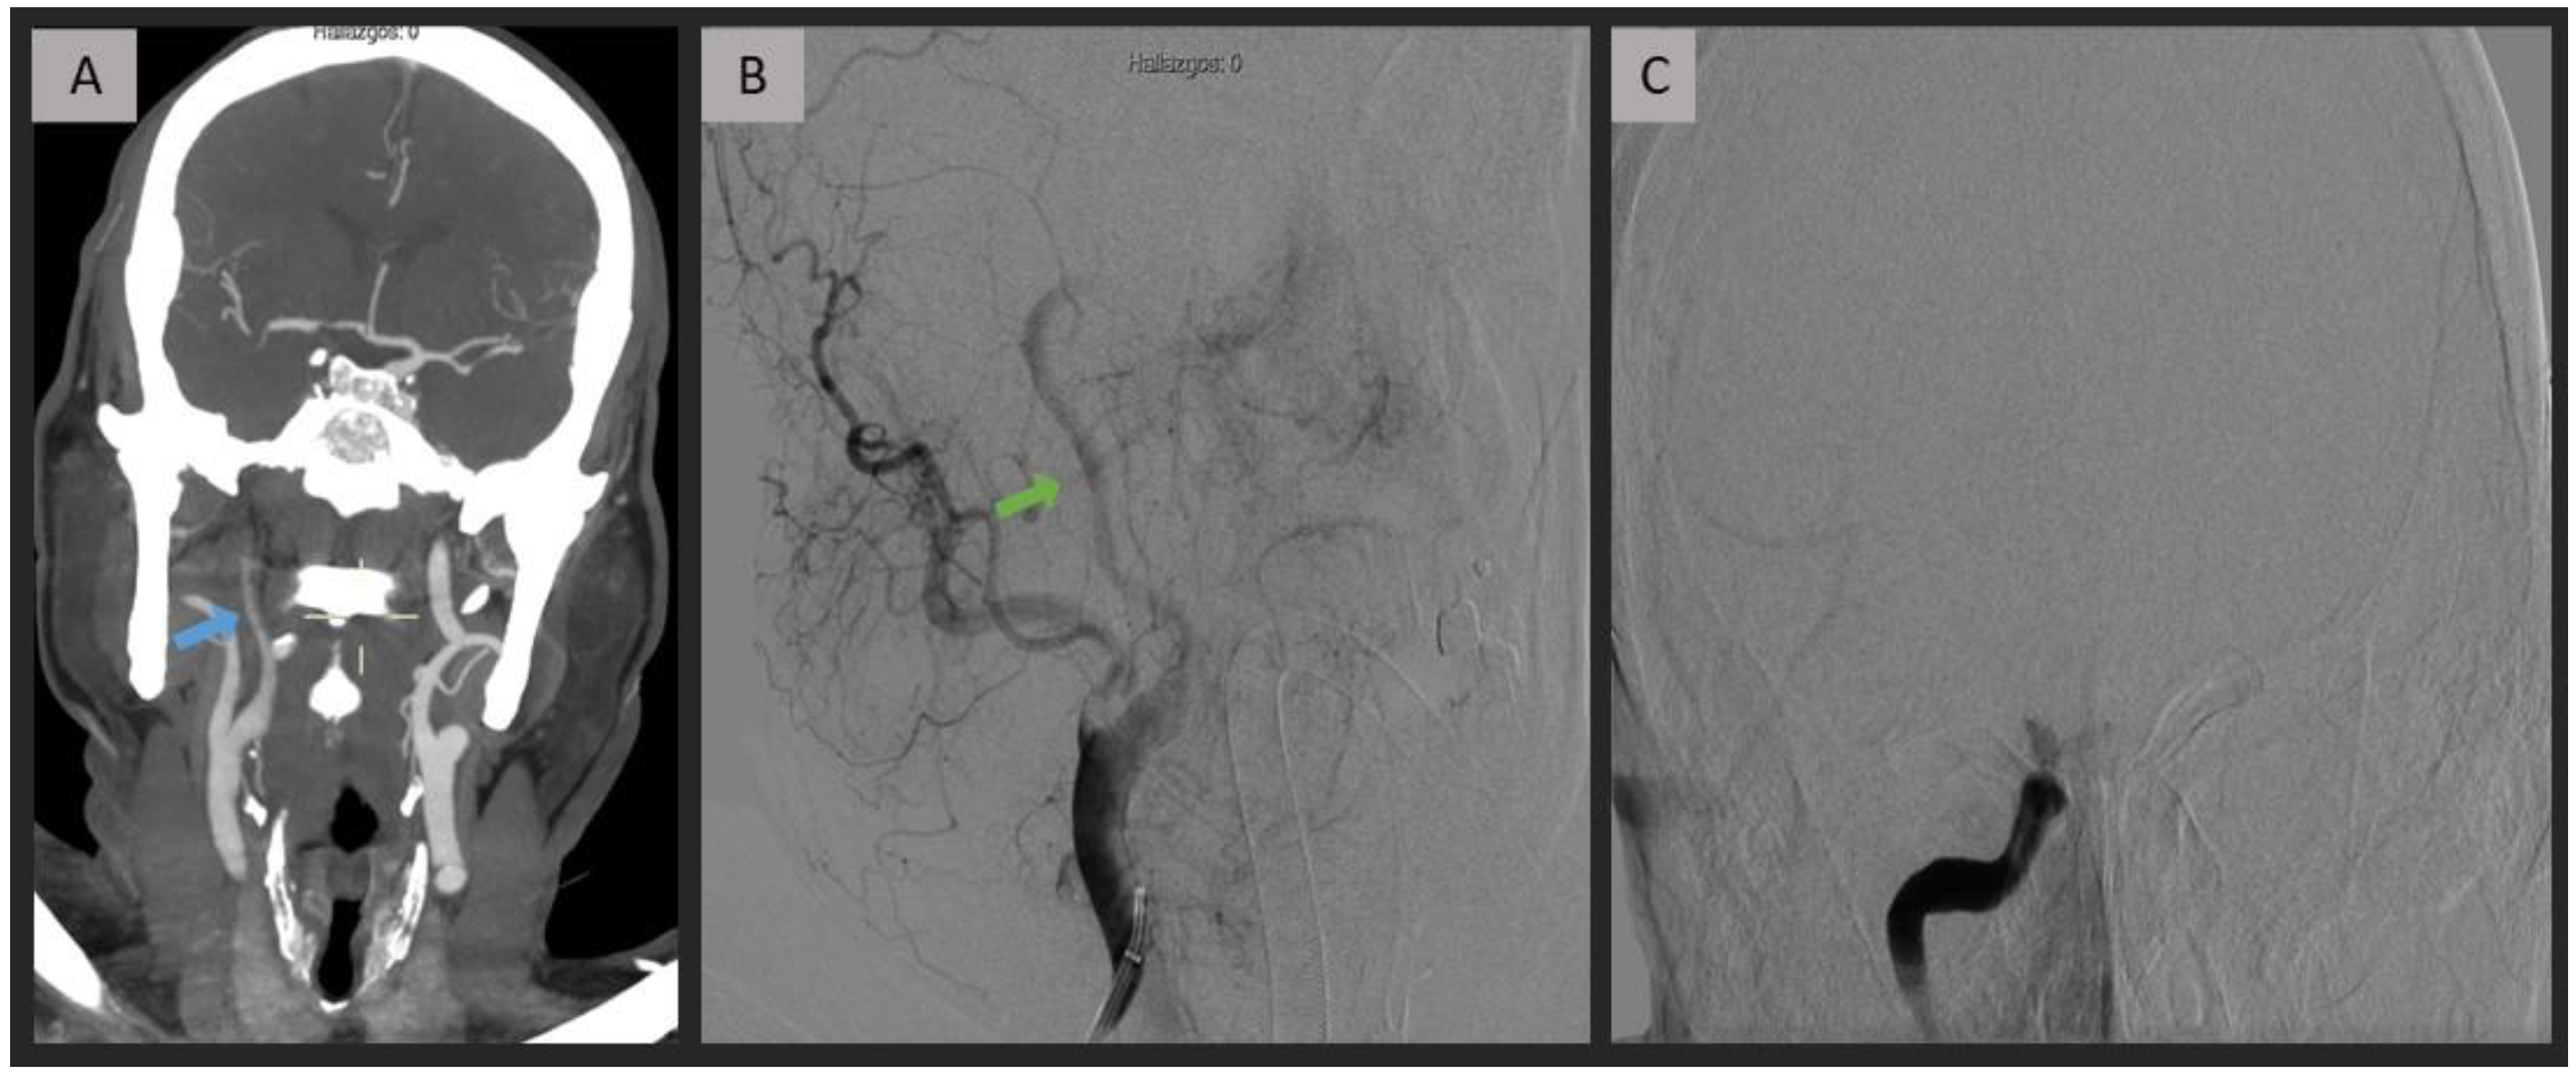

2.4. CTA Analysis

2.5. DSA Analysis

3. Results

4. Discussion